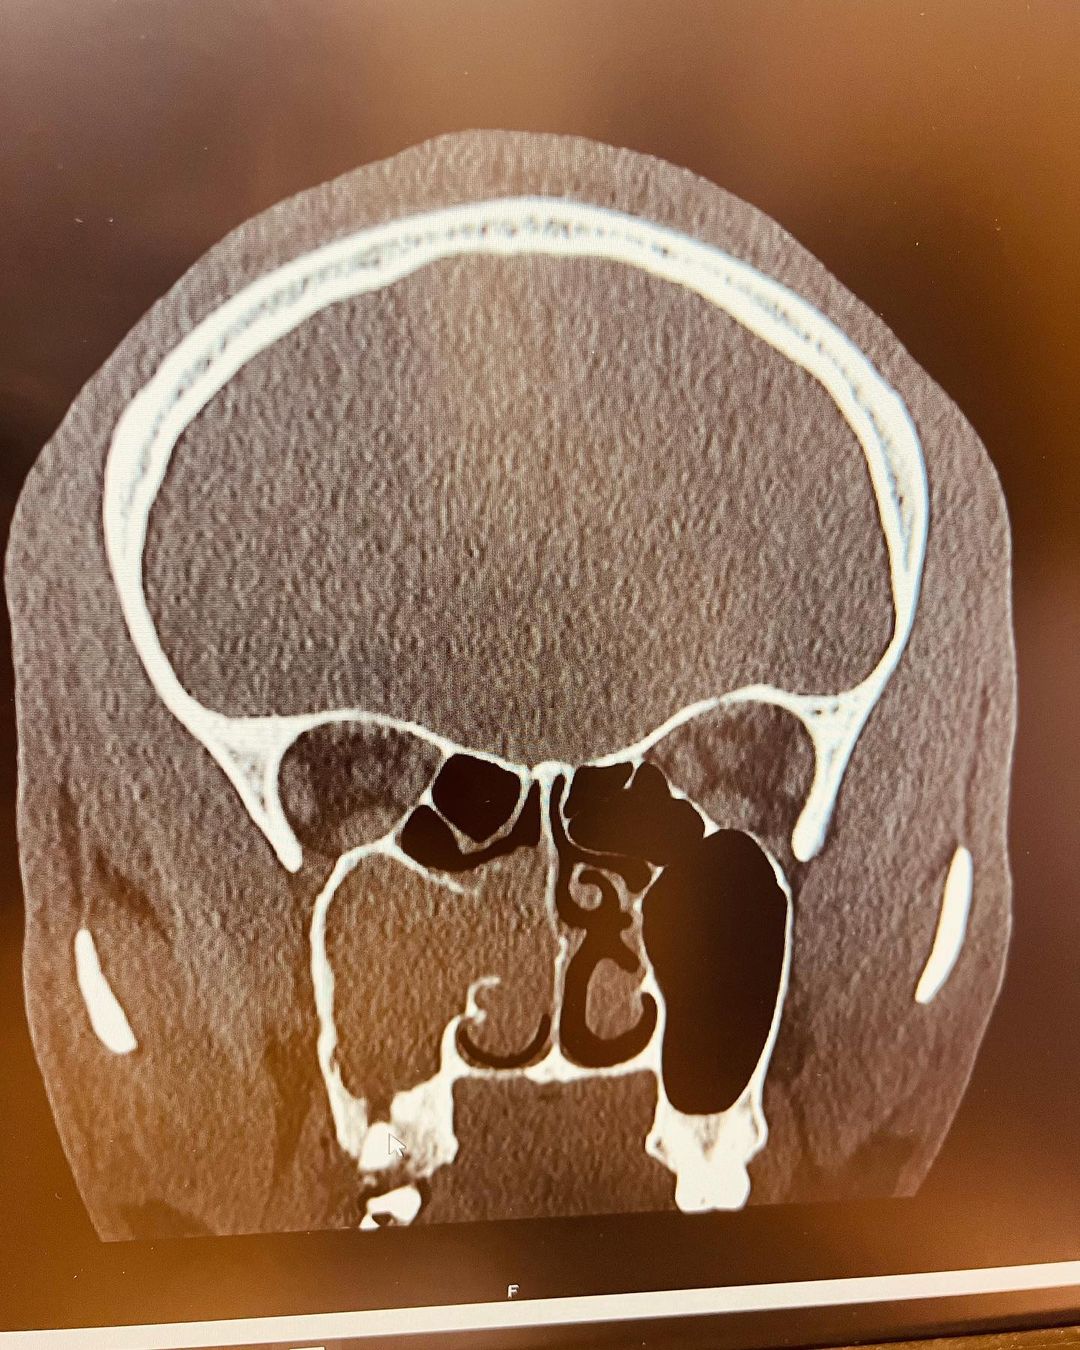

Afterwards I decided to return home to New York, all these while the sinus issue hasn’t given me any relive almost 1 year after. I decided to see an allergist and between January and March 2021, I have had multiple doctors appointments and test which the scan results came back very unpleasant. Half of my right face/nostril was blocked and I was only breathing from my left nostril. At this stage I wake up with mucus from my right nostril every single day.

PS: The grey area on the scan photo is the blocked part of my Face/Nostril. Big thanks to my friends and loved ones that took care of me when I was sick, May almighty God meet you at your point of needs 🙏🏾”.